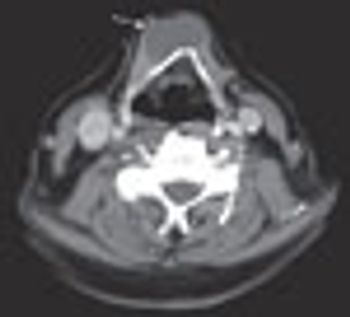

For several years, an asymptomatic, firm, nontender mass had been growing on the neck of a 54-year-old-man, slightly left of midline at the level of the hyoid bone. Thyroid function tests were normal. What does it indicate?